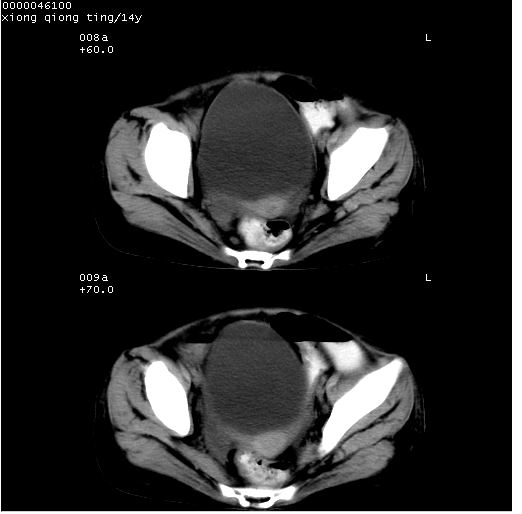

患儿 女,14岁。不规则发热一周,偶感头痛,无抽搐及呕吐。pe:神清,精神差,双侧瞳孔等大等圆,对光反射敏感,双肺未闻及明显啰音,心音有力,腹部触之似揉面感,下腹压痛,无反跳痛。

腹部b超提示:子宫缩小,盆腔积液,肝实质回声密集。

中下腹及盆腔ct轴位平扫+增强扫描(层厚10mm,螺距1.0,重建间隔10mm),图像如下:

(注:患儿检查当日上午9时口服胃肠道对比剂,下午3时许行ct扫描检查,未行对比剂直肠保留灌肠,检查当日患儿腹泻)

中下腹及盆腔ct轴位扫描(ps+ce)提示:腹部肠管明显充气扩张,并见数个不同宽度之气液平面;疑不全性肠梗阻或肠郁张。临床会诊考虑为患儿腹泻,肠郁张所致;后来未经特殊处理,患儿大便恢复正常,亦无腹胀。

临床出院诊断:1)结核性腹膜炎。2)腹膜后淋巴结结核。3)脂肪肝。